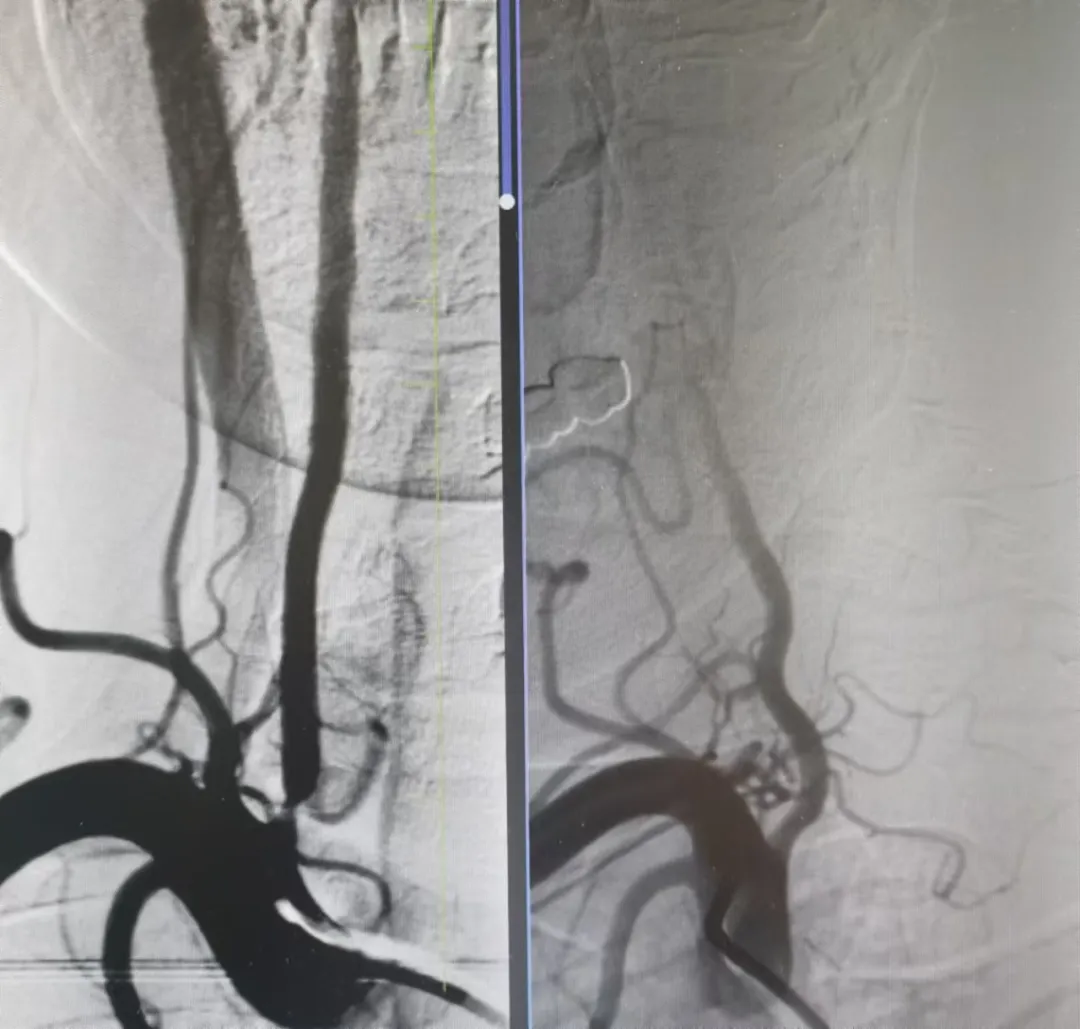

家屬同意后,神經(jīng)介入科團(tuán)隊(duì)迅速給予行腦血管造影,結(jié)果提示:右側(cè)椎動(dòng)脈重度狹窄。朱洪波副主任表示:該處一旦發(fā)生循環(huán)梗死,輕則癱瘓?jiān)诖病⒅貏t昏迷不醒甚至危及生命,建議盡快對(duì)重度狹窄血管積極處理。家屬對(duì)患者病情及治療方案詳細(xì)了解后,決定接受介入手術(shù)治療。

手術(shù)在局麻下施行,通過經(jīng)橈動(dòng)脈入路,予以行右側(cè)椎動(dòng)脈起始處重度狹窄球囊擴(kuò)張術(shù),經(jīng)股動(dòng)脈穿刺,微導(dǎo)絲送入球囊至病變狹窄部位進(jìn)行擴(kuò)張,擴(kuò)張后造影提示狹窄部位擴(kuò)張滿意,基底動(dòng)脈血流明顯改善,手術(shù)順利結(jié)束。術(shù)后陳大叔上述癥狀完全恢復(fù),大叔妻子感激地說:“感謝國(guó)文醫(yī)院的積極救治,來的時(shí)候老陳都暈的無法走路,現(xiàn)在都能自己行走了,太感謝了?!?/p>

1個(gè)月前姜大爺(化名)反復(fù)出現(xiàn)右側(cè)肢體抽搐癥狀,碾轉(zhuǎn)當(dāng)?shù)囟嗉裔t(yī)院治療,效果不理想,嚴(yán)重影響日常生活,在家人的陪同下來到國(guó)文醫(yī)院神經(jīng)介入科。入院后給予行頭MRI彌散+頸部MRA提示:左側(cè)大腦半球分水嶺性腦梗死,左側(cè)頸內(nèi)動(dòng)脈起始處重度狹窄,給予行DSA提示:左側(cè)頸內(nèi)動(dòng)脈起始處重度狹窄至閉塞前改變。

丁金明主任指出:患者反復(fù)抽搐原來是血管狹窄惹得禍,跟患者家屬交代病情后,患者家屬要求血管內(nèi)介入治療,在導(dǎo)管室傾力配合下,順利完成“左側(cè)頸內(nèi)動(dòng)脈起始處重度狹窄支架植入術(shù)”,術(shù)后患者未再出現(xiàn)抽搐癥狀,術(shù)后在醫(yī)護(hù)人員的精心治療和悉心護(hù)理下,患者恢復(fù)良好即將出院。